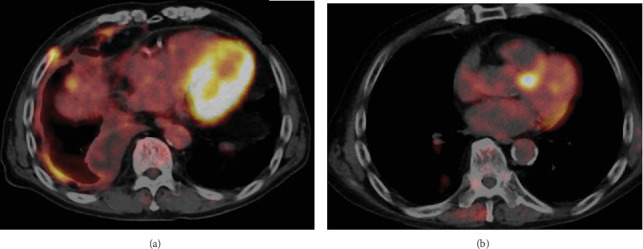

我们描述了两例经历了严重的多重免疫相关不良事件(irAEs)、治疗中断和类固醇治疗的患者。尽管存在这些挑战,但它们取得了超出预期的显著抗肿瘤效果。多种肿瘤显示免疫检查点抑制剂的抗肿瘤作用可能与irae的强度相关,但对恶性胸膜间皮瘤(MPM)的研究很少报道。我们的两个病例表现出比平常更强的irae。这两个病例仍然表现出完全缓解(CR)或接近CR部分缓解,表明irAEs与MPM抗肿瘤作用之间存在相关性。

We describe two patients who experienced serious multiple immune-related adverse events (irAEs), treatment interruption, and steroid administration. Despite these challenges, they achieved a remarkable antitumor effect beyond the expected. Various carcinomas demonstrated a possible correlation between the antitumor effect of immune checkpoint inhibitors and the intensity of irAEs, but few studies report on malignant pleural mesothelioma (MPM). Our two cases exhibited much stronger irAEs than usual. These two cases still demonstrated a complete response (CR) or near CR partial response, indicating a correlation between irAEs and the antitumor effect in MPM.